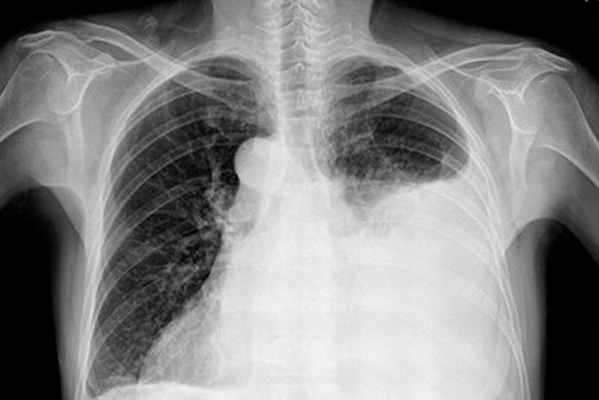

Специальные исследования • Обзорная рентгенография органов грудной клетки: коллапс лёгкого, горизонтальный уровень жидкости, смещение (флотация) средостения в здоровую сторону • Пункция плевральной полости: кровь; при продолжающемся кровотечении полученная при пункции кровь сворачивается (положительная проба Ривилуа–Грегуара).